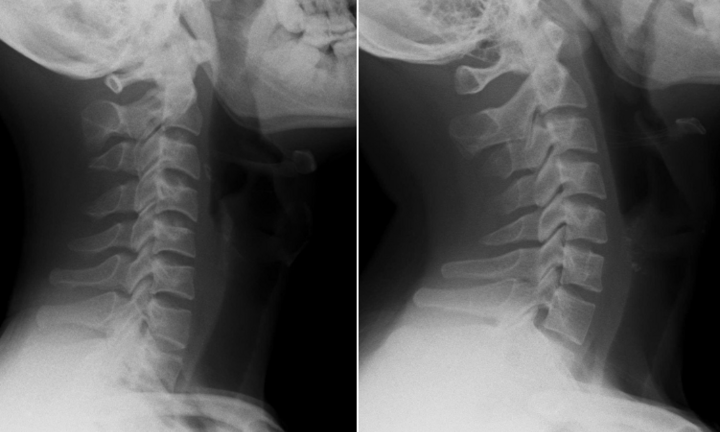

Đau cổ vai gáy dai dẳng, nam nhân viên văn phòng 26 tuổi đi khám thì bất ngờ phát hiện cột sống bị mất đường cong sinh lý, thẳng như cây gậy.

Đau cổ vai gáy dai dẳng, nam nhân viên văn phòng 26 tuổi đi khám thì bất ngờ phát hiện cột sống bị mất đường cong sinh lý, thẳng như cây gậy.